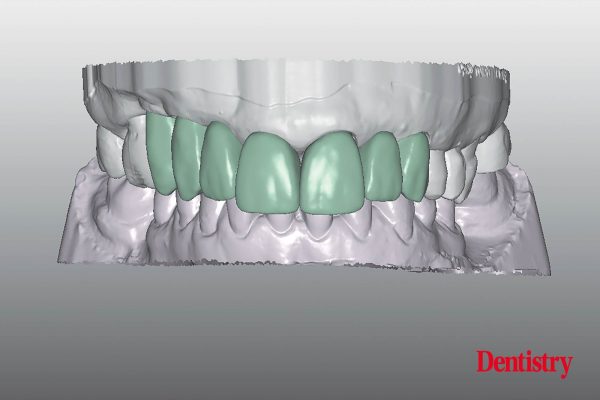

Delicate anterior restoration: non-prep veneers made from hybrid ceramics

Ting-Huan Lai, Cheng-Han Li and Sharon Chou show how the dual ceramic-polymer network structure of Vita Enamic allow non-prep veneers…

Dentistry